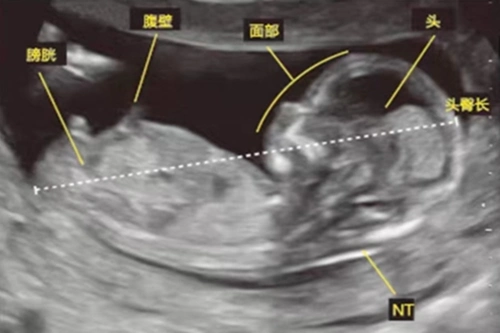

怀孕13周,胎儿发育情况怎么样?该怎样养护胎儿比较好?

怀孕13周四维彩超产检实录,幸运的拍到了宝宝朝我们挥手致意!